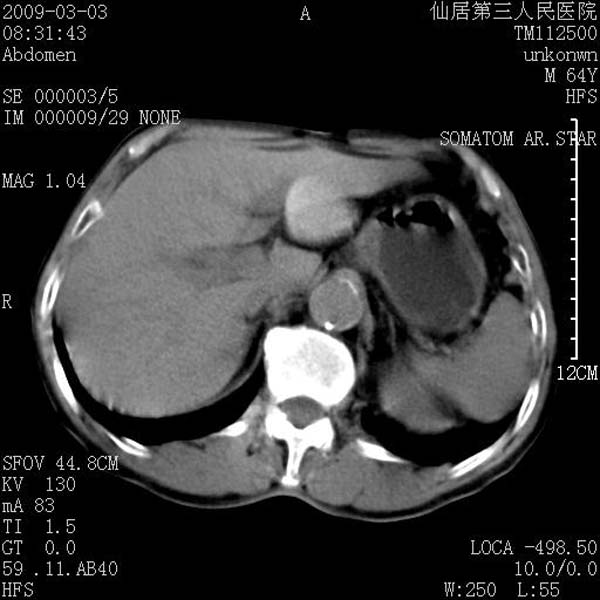

标题: CT18469:男性,64y,体检B超示肝脏低回声肿块,有胃溃疡手术 [打印本页]

患者,男性,64y,体检b超示肝脏低回声肿块,有胃溃疡手术史。

从平扫及增强的特点来看,支持肝脏腺瘤并出血。

ct值呢?感觉没强化,象囊性。

考虑肝囊肿并出血可能性大.

考虑高密度囊肿可能性大